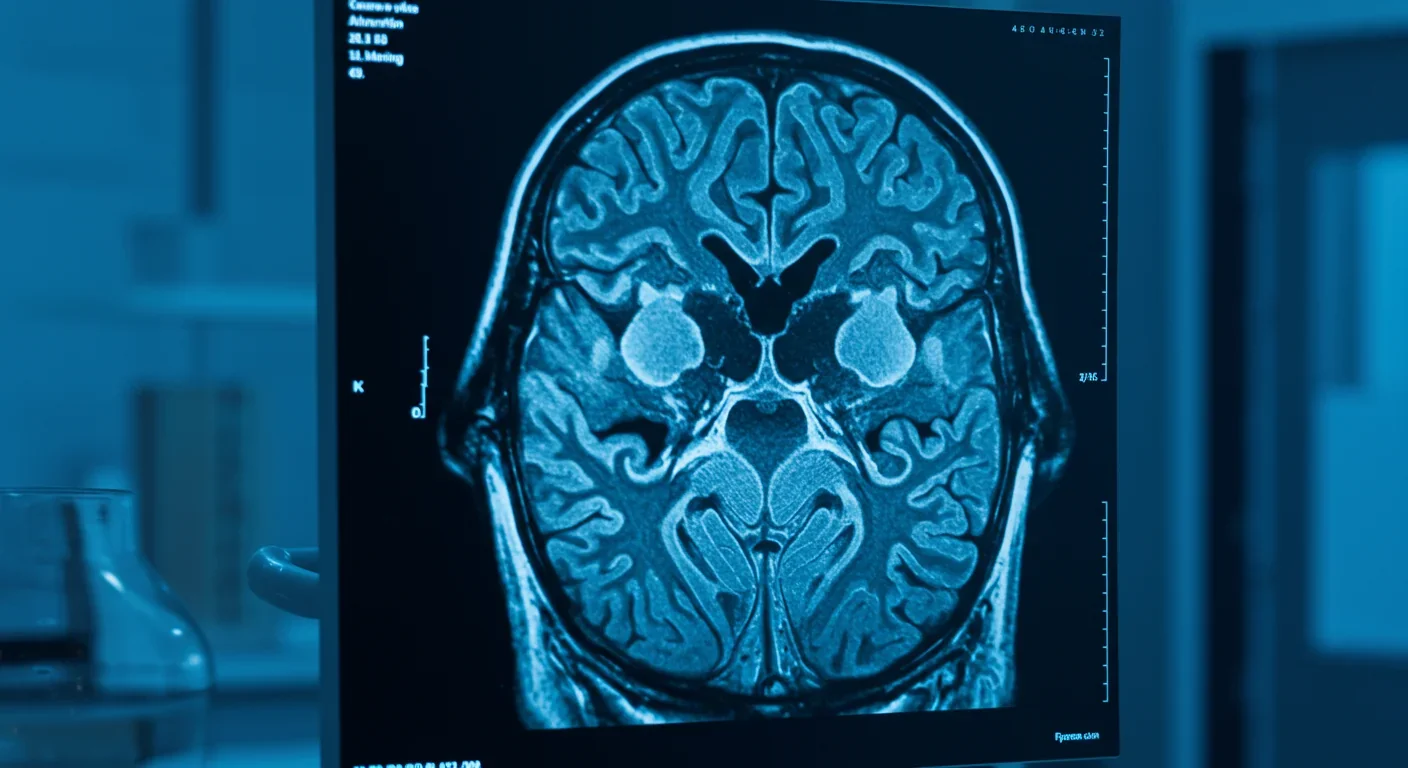

The phenomenon goes deeper than most realize. When you're part of a crowd, specific regions of your brain light up or dim in patterns that researchers can now predict and measure. Your prefrontal cortex - the brain's executive control center - reduces its activity, while your limbic system revs into high gear. The result? You become more emotional, less analytical, and remarkably synchronized with the people around you. Recent neuroimaging studies have captured these changes in action, revealing why rational individuals can transform into something entirely different when the crowd swells.

For decades, crowd psychology remained frustratingly vague - more philosophical speculation than hard science. That changed when neuroscientists started putting people in fMRI machines and measuring what actually happens when humans interact. The breakthrough came from hyperscanning technology, which simultaneously records brain activity from multiple people. What researchers discovered was stunning: brains actually synchronize during social interaction, creating coordinated electrical patterns that predict how groups will behave.

Research shows that crowd situations activate the limbic system while reducing prefrontal cortex activity. An fMRI study on group versus individual problem-solving found distinct neural patterns: solo thinking engaged more of the dorsolateral prefrontal cortex, associated with working memory and executive function. Group contexts shifted activity toward regions involved in social processing and emotion regulation. Essentially, your brain stops treating the situation as a logic puzzle and starts treating it as a social event.